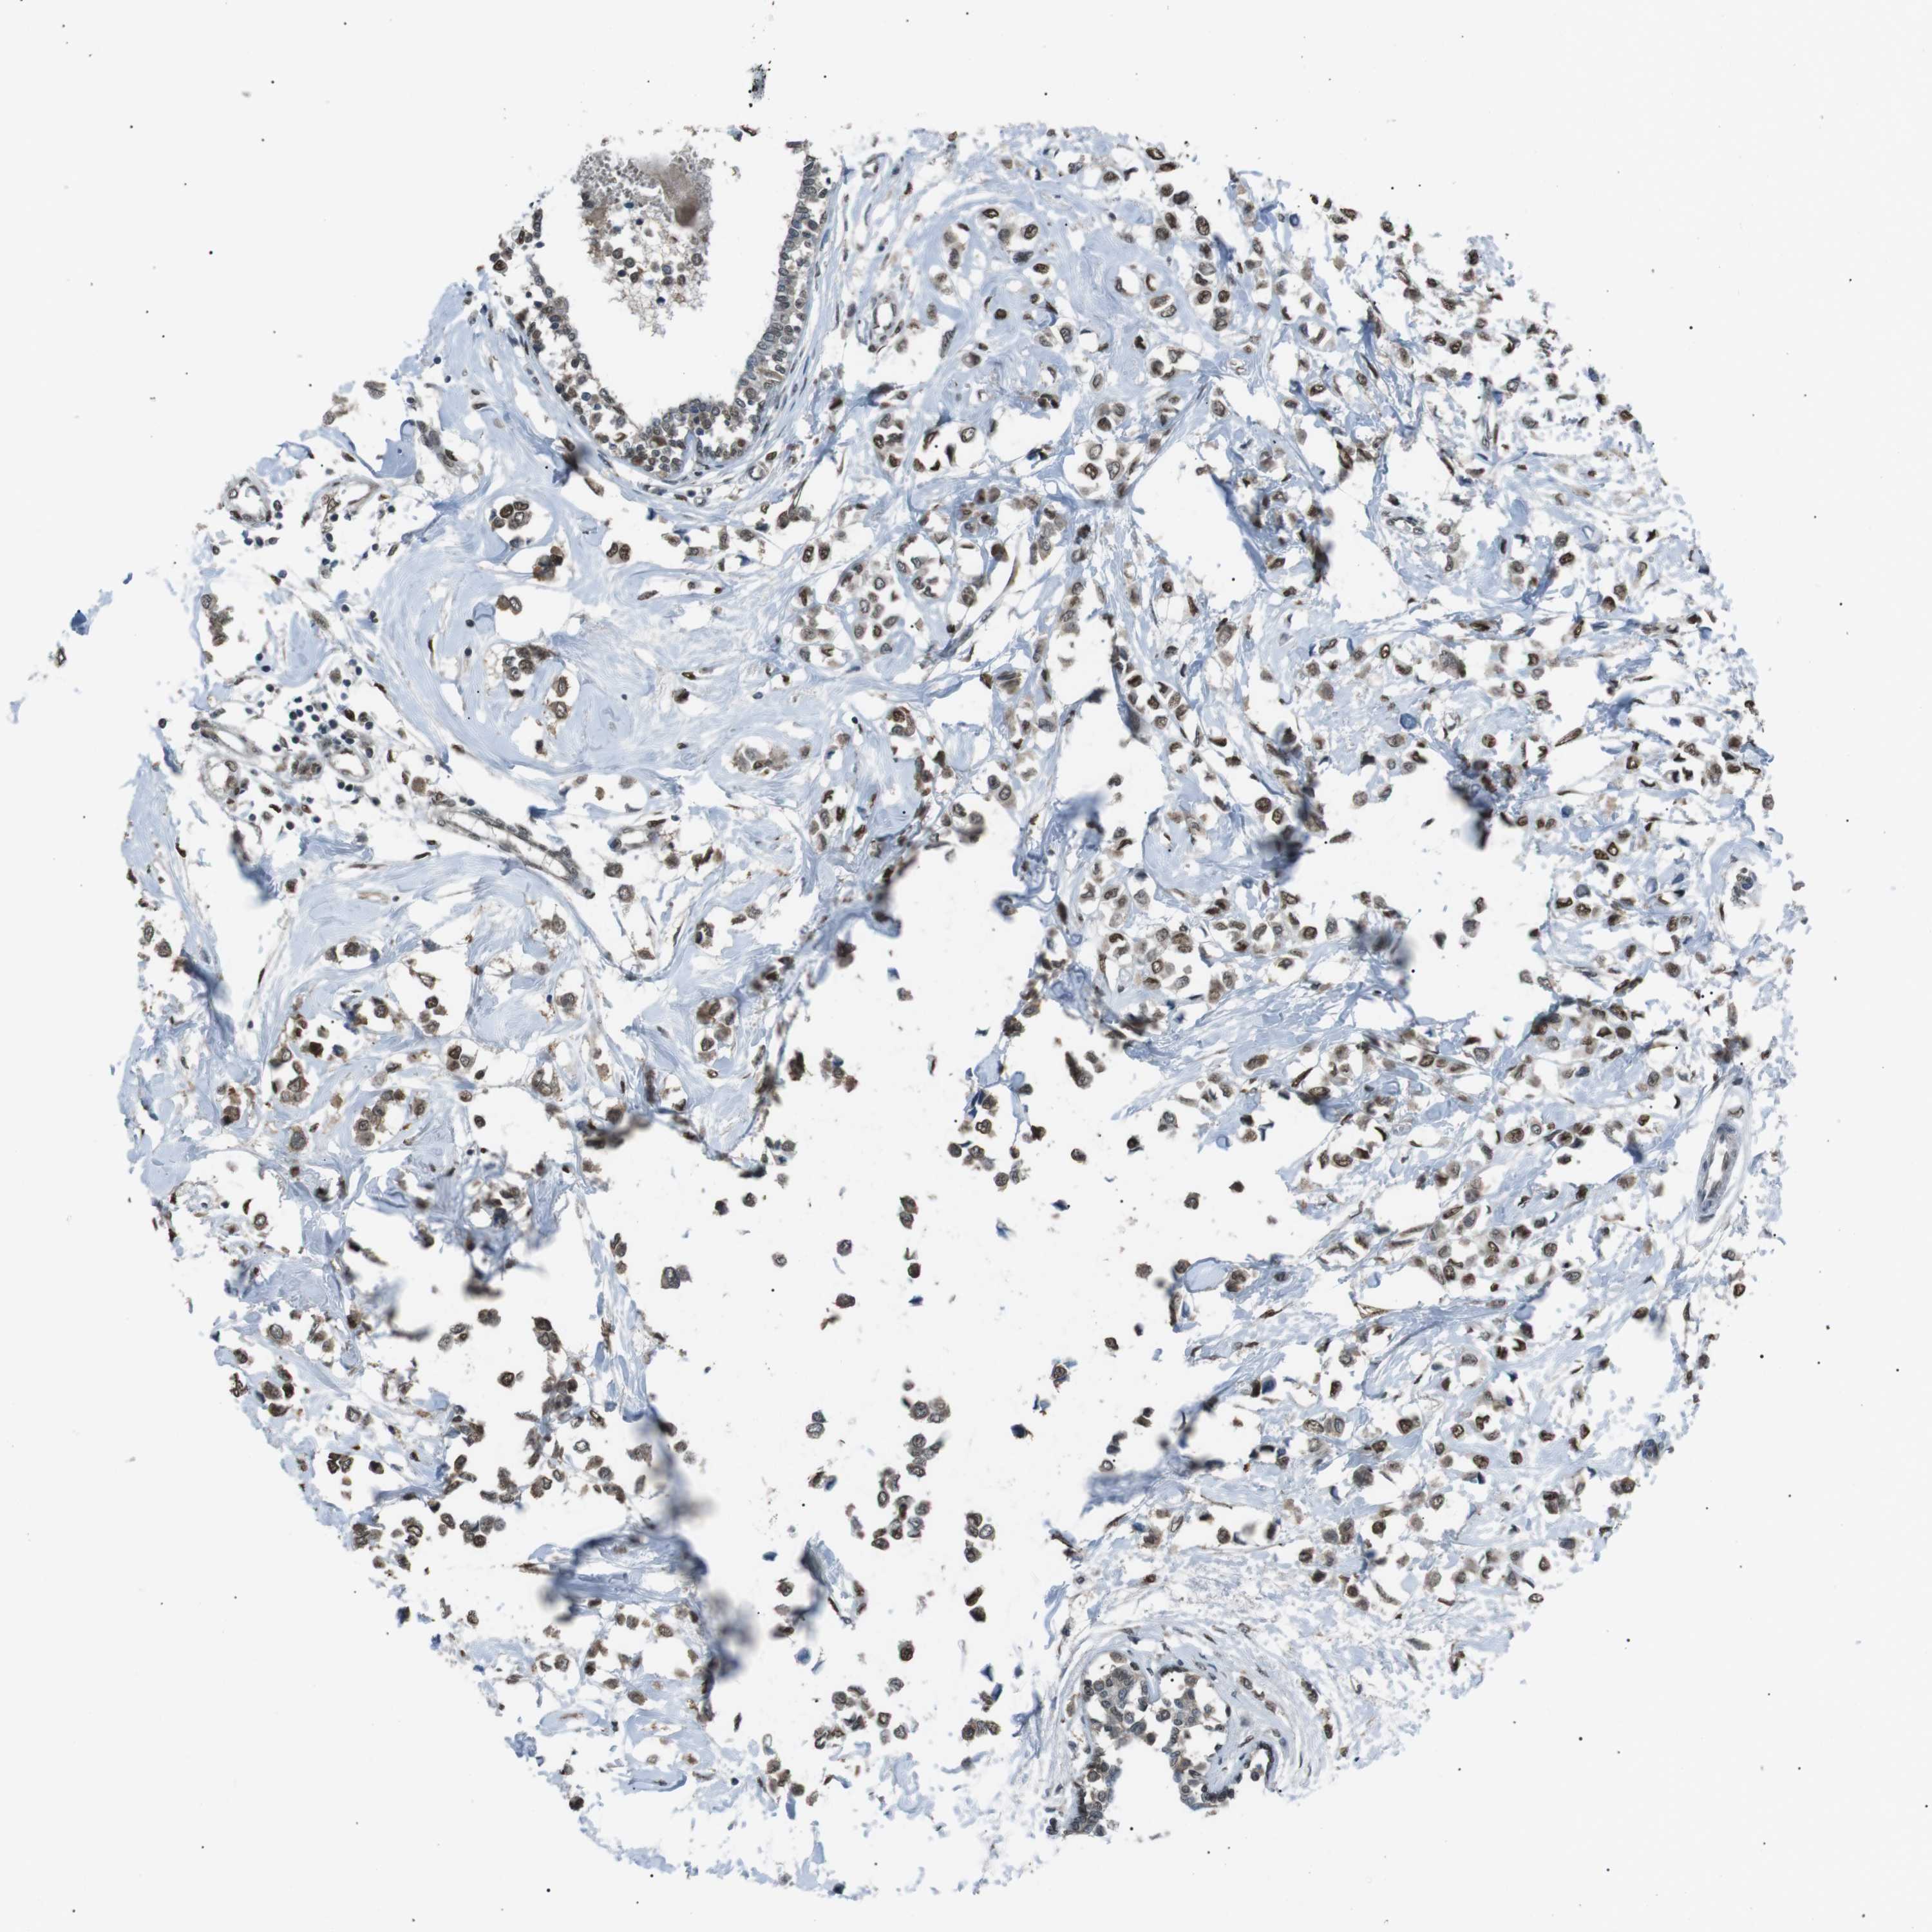

BRCA TCGA BRCA VALIDATION PROTEIN EXPRESSION